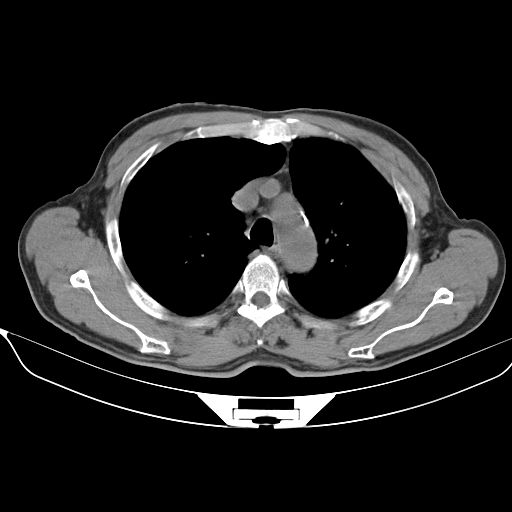

以下是引用心路寻觅在2010-3-1 10:23:00的发言:[br]1、考虑左肺上叶周围型肺癌[br]2、右上肺陈旧性病灶。[br][br][本贴已被 心路寻觅 于 2010-3-1 10:40:18 修改过]

以下是引用shuiyuan在2010-3-1 10:45:00的发言:[br]考虑左肺上叶中心型肺癌伴阻塞型炎症,邻近胸膜受侵。